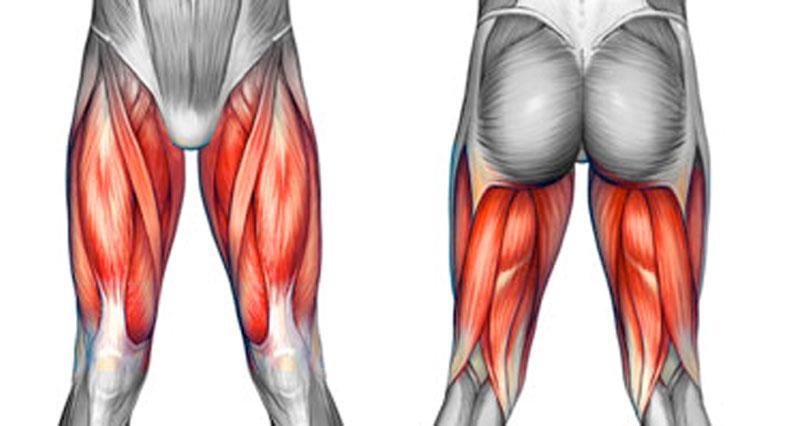

Chấn thương cơ đùi lâu khỏi không chỉ gây đau đớn kéo dài mà còn ảnh hưởng nghiêm trọng đến khả năng vận động. Đặc biệt, những tổn thương như chấn thương cơ đùi sau hay chấn thương lật cổ chân thường đi kèm với nguy cơ suy giảm chức năng cơ bắp, làm tăng nguy cơ tái phát. Vậy đâu là hướng xử lý đúng đắn giúp phục hồi nhanh chóng, ngăn ngừa biến chứng và đưa cơ bắp trở lại trạng thái tối ưu?

Chấn thương cơ đùi lâu khỏi không chỉ là vấn đề đơn giản về căng cơ mà có thể gây ra những tổn thương phức tạp hơn như rách cơ, tổn thương mô liên kết hoặc thậm chí viêm mạn tính. Khi gặp phải những chấn thương này, quá trình hồi phục kéo dài và khó khăn nếu không được điều trị đúng cách.

Chấn thương cơ đùi, đặc biệt là chấn thương cơ đùi sau, không chỉ gây đau nhức mà còn ảnh hưởng đến khả năng vận động nếu không được xử lý đúng cách. Trong nhiều trường hợp, tình trạng này có thể kéo dài, khiến người bệnh gặp khó khăn trong sinh hoạt và tập luyện.

Nếu không được chẩn đoán và điều trị kịp thời, chấn thương có thể để lại di chứng như mô sẹo xơ cứng, suy giảm sức mạnh cơ hoặc tăng nguy cơ tái phát. Do đó, nhận biết sớm các dấu hiệu bất thường là yếu tố quan trọng giúp người bệnh có phương pháp can thiệp đúng đắn. Dưới đây là những triệu chứng phổ biến cảnh báo chấn thương cơ đùi đang kéo dài và có nguy cơ diễn biến phức tạp hơn.

3.2. Cảm giác yếu cơ, chân mất sức, vận động kém linh hoạt

Bên cạnh đau nhức, nhiều bệnh nhân bị chấn thương cơ đùi lâu khỏi còn nhận thấy chân bị yếu đi đáng kể, đặc biệt khi cố gắng thực hiện các động tác yêu cầu sức mạnh hoặc sự linh hoạt của cơ đùi.

Nếu tổn thương xảy ra ở cơ tứ đầu đùi (cơ đùi trước), người bệnh có thể gặp khó khăn trong việc duỗi thẳng chân hoặc giữ thăng bằng khi đứng lâu. Trong trường hợp chấn thương cơ đùi sau, việc gập gối hoặc thực hiện các động tác đẩy mạnh chân về phía sau có thể trở nên khó khăn hơn.

Sự suy giảm sức mạnh cơ không chỉ ảnh hưởng đến hiệu suất vận động mà còn làm tăng nguy cơ chấn thương tái phát, do cơ bắp không còn đủ sức chịu tải như trước. Nếu không can thiệp kịp thời, cơ có thể teo nhỏ dần do không được kích thích hoạt động đúng cách, kéo dài thời gian hồi phục.